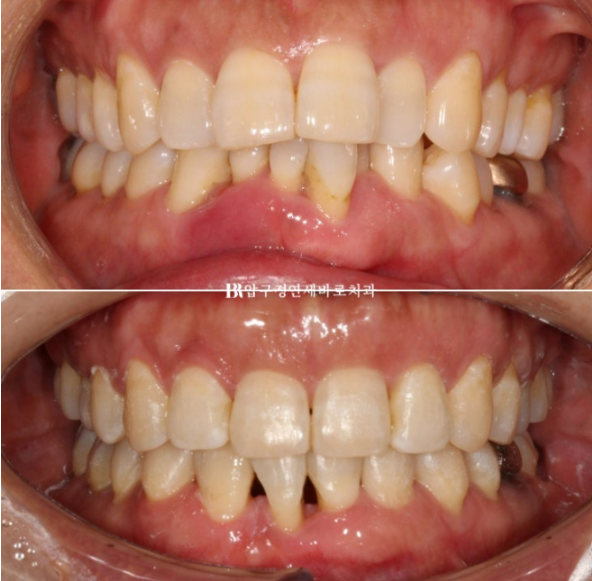

치료 시작 1년 6개월 만인 이번달에 치료를 마무리 했습니다.

파란 화살표는 송곳니이고 앞니 자리로 잘 이동했습니다.

교합도 좋습니다.

2022.11~24.05

파란 화살표 앞니 자리에 와 있는 송곳니입니다.

앞니쪽 치주염은 꾸준히 관리로 잘 치료가 되었고 앞니 뻗침은 개선이 되었습니다.

앞니 4개가 있어야 할 자리에 앞니 2개로 마무리를 하면 블랙트라이앵글이 생길 수 밖에 없습니다.

특히 치주염으로 부었던 잇몸이 가라앉으면서 블랙트라이앵글이 더 커보이는 것 입니다.

이 부분은 교정 후에도 치간칫솔로 잘 닦아주면서 치석이 들어차지 않게끔 스스로 관리 하도록 당부드렸습니다.

간혹 이 부분을 메우고 싶어하는 경우가 있으나 워낙 치주염이 심했던 부위여서 추천드리지는 않습니다.